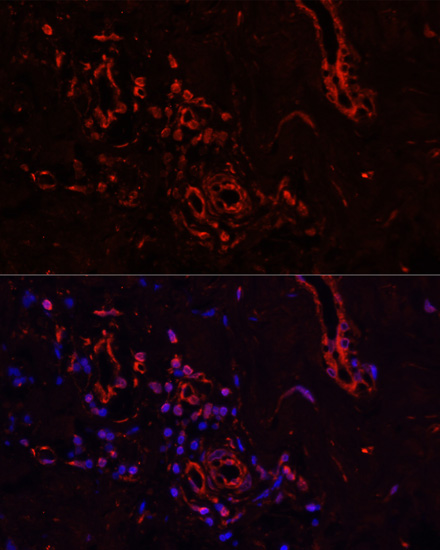

Immunofluorescence analysis of human breast cancer using COL1A1 at dilution of 1:100. Blue: DAPI for nuclear staining.

Immunofluorescence analysis of human breast cancer using COL1A1 at dilution of 1:100. Blue: DAPI for nuclear staining.